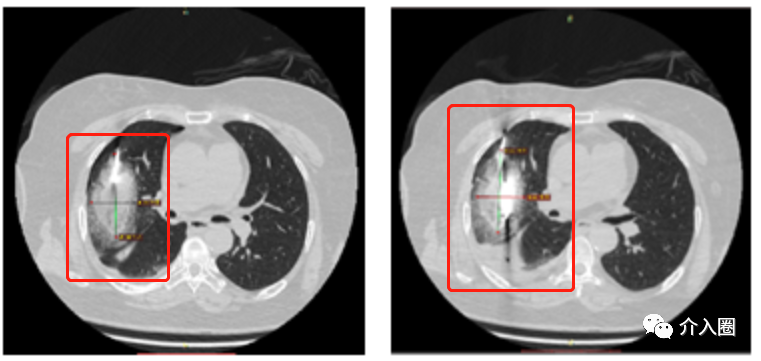

肺轉(zhuǎn)移癌應用實例(來源:康博刀官方資料)

患者信息:肺轉(zhuǎn)移癌

治療方案及過程:康博刀單根消融針,消融范圍達腫瘤外緣1cm

治療結果:復查顯示病灶條索狀改變,基本消失。

▲圖5 術前

▲圖6 術中冷凍消融治療

▲圖7 術后6個月復查